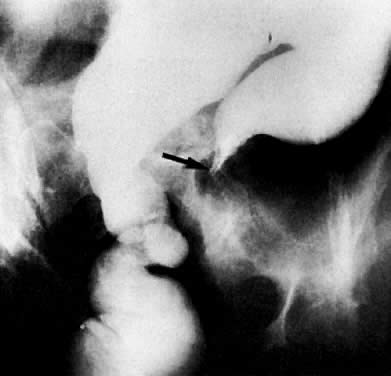

Colon examination shows bowel obstruction (arrow) in sigmoid colon. Patient has advanced endometrial carcinoma.

A 62-year-old woman with cervical cancer. Small-bowel follow-through shows encasement of the distal jejunum (arrow) causing proximal obstruction.

Colon examination shows displacement of the sigmoid colon by a pelvic mass from endometrial carcinoma.